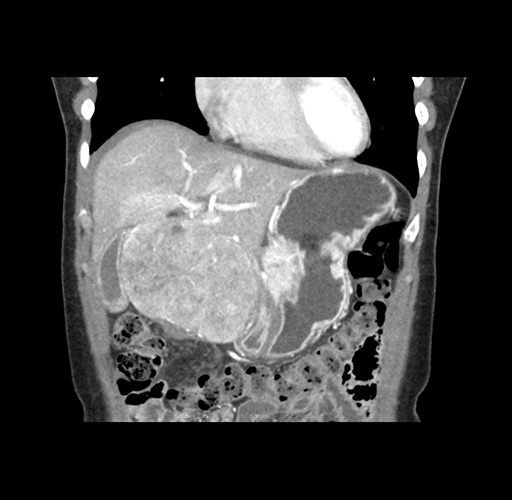

Imaging Analysis

Look through the patient's CT scan to identify any areas of concern for the necessary procedure.

Based on your CT findings, which issue(s) would give reason for "planned slowing down moment(s)" in this case?

Considering a standard left lateral sectionectomy procedure, what step(s) of the operation would you do differently in this case ?